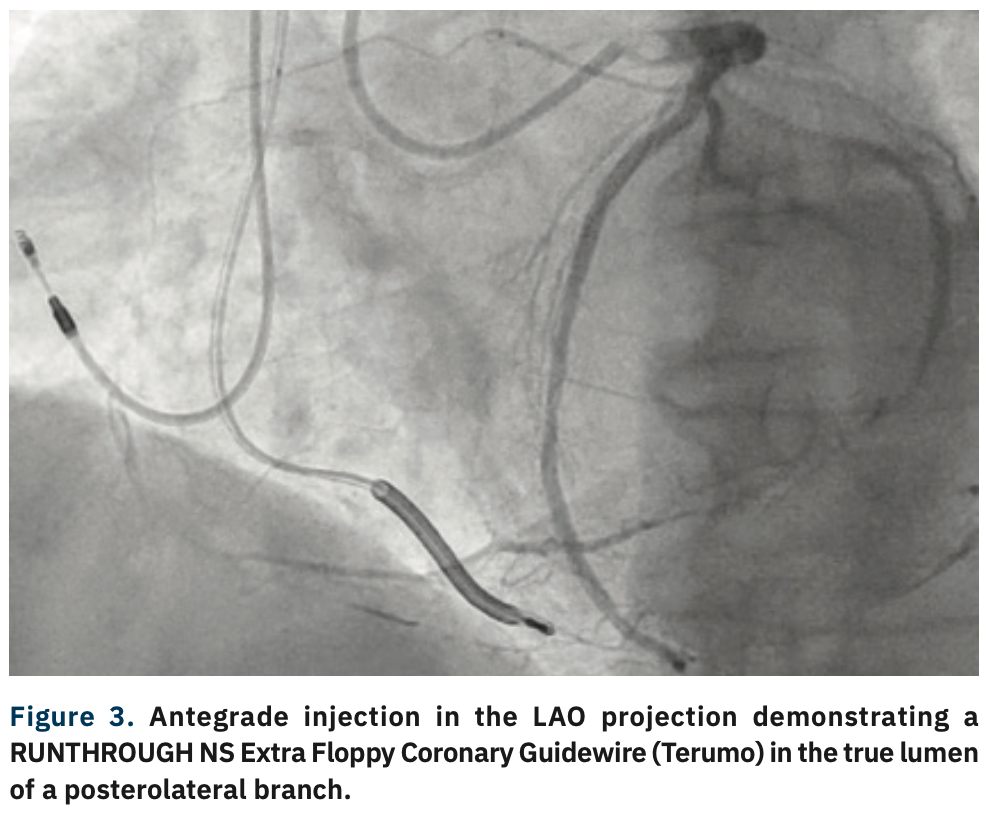

A 6 Fr, 10 cm GLIDESHEATH SLENDER® Introducer Sheath (Terumo) was used to gain access in the right radial and left distal radial arteries. Two hundred (200) mcg of intra-arterial nitroglycerin and 200 mcg of intra-arterial nicardipine were given for each access. Each access point was exchanged for a 6 Fr, 85 cm R2P DESTINATION SLENDER Guiding Sheath (Terumo) over a 180 cm, .035-inch J-tipped guidewire. A 6 Fr Amplatz Left (AL) 0.75 VISTA BRITE Guiding Catheter (Cordis) was used to engage the right coronary artery and a 6 French XB 3.5 ADROIT™ Guiding Catheter (Cordis) was used to engage the left coronary artery. A Twin-Pass® Dual Access microcatheter (Teleflex) was advanced over the RUNTHROUGH® NS Coronary Guidewires (Terumo) into the proximal right coronary artery. A Fielder® XT-A (Asahi Intecc) was then used in an attempt to engage the proximal cap, but was without success. It was exchanged for a MIRACLEBROS® 6 (Asahi Intecc), which penetrated the proximal cap, but was unsuccessful at crossing the distal cap. The Twin-Pass Dual Access microcatheter was exchanged for a Turnpike® LP microcatheter (Teleflex) but was also without success. The Turnpike was then exchanged for a Fielder XT-A, then a HI-TORQUE PILOT™ 200 guidewire (Abbott Vascular), and finally, a CONFIANZA® Pro 12 guidewire (Asahi Intecc), all of which were unable to cross the distal cap true-to-true lumen. Instead, a HI-TORQUE PILOT 200 guidewire was knuckled, and used to perform subintimal tracking and re-entry technique into the mid right coronary artery. The HI-TORQUE PILOT 200 guidewire was first exchanged for a RUNTHROUGH NS Extra Floppy guidewire to wire the RV marginal branch and then exchanged for a GRAND SLAM® guidewire (Asahi Intecc). A 2.5 mm x 20 mm EMERGE PTCA Dilation Catheter (Boston Scientific) was used to pre dilate the lesion, followed by a 3.0 mm x 20 mm NC EMERGE PTCA Dilation Catheter (Boston Scientific). Angiography showed antegrade flow into the RV marginal, but not into the posterior descending artery or the posterolateral branches. Two SYNERGY EES PtCr coronary stents (Boston Scientific), a 3.5 mm x 38 mm and a 3.5 mm x 12 mm, were deployed proximally. A RUNTHROUGH NS Extra Floppy coronary guidewire with a Turnpike LP was then used to wire the posterior descending artery/posterolateral branches and the RUNTHROUGH NS Extra Floppy coronary guidewire was exchanged for a GRAND SLAM guidewire. The Turnpike LP was removed using a DOC Guide Wire Extension (Abbott Vascular). A 2.75 mm x 38 mm SYNERGY EES PtCr coronary stent was deployed from the posterolateral into the distal right coronary artery, followed by a 3.5 mm x 38 mm SYNERGY EES PtCr coronary stent. All stents were deployed at nominal pressure. The first GRAND SLAM coronary guidewire was removed. A 3.5 mm x 20 mm SYNERGY EES PtCr coronary stent was then deployed, overlapping the first and second 3.5 mm x 38 mm stents. These stents were then post dilated with a 4.0 mm x 20 mm NC EMERGE PTCA Dilation Catheter. A 3.5 mm x 12 mm SYNERGY EES PtCr coronary stent was deployed at the ostium of the right coronary artery and post dilated with a 4.0 mm x 20 mm NC EMERGE PTCA Dilation Catheter. Final angiography showed TIMI-III flow, no residual stenosis, and no perforation or dissection.